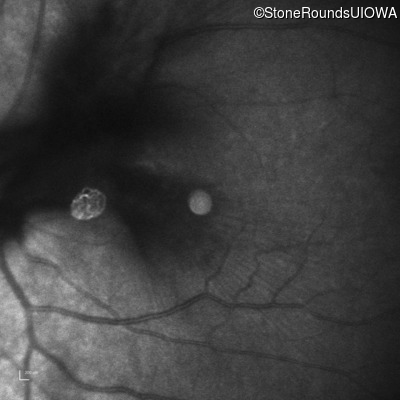

Fluorescein Angiography - Right - 20/50 -1 sc

Exemplar

Fluorescein Angiography - Left - 20/60 sc